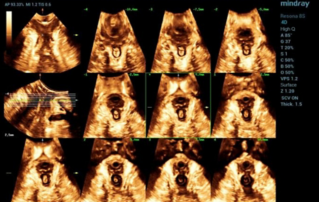

골반저 3D 및 4D 초음파

리플레이 | 웨비나 | 여성 진료 | 여성 진료 | 세계 산부인과 초음파 학회

태아 비뇨기 기형

태아 신장 및 요로의 선천적 기형